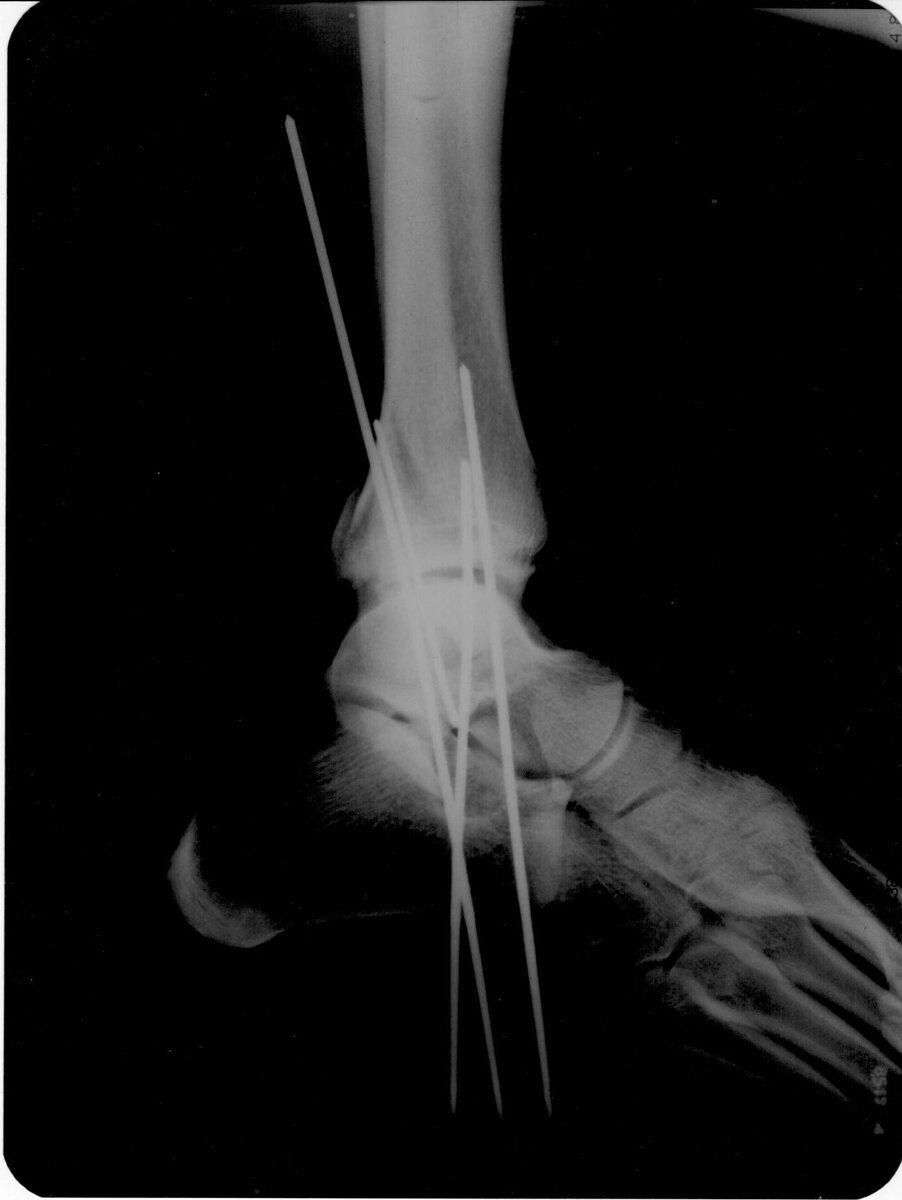

Благодарен хирургам, которым удалось без операции собрать мою ногу и зафиксировать её спицами. Причем один из них был интерном. Это было круто. Благодарю!